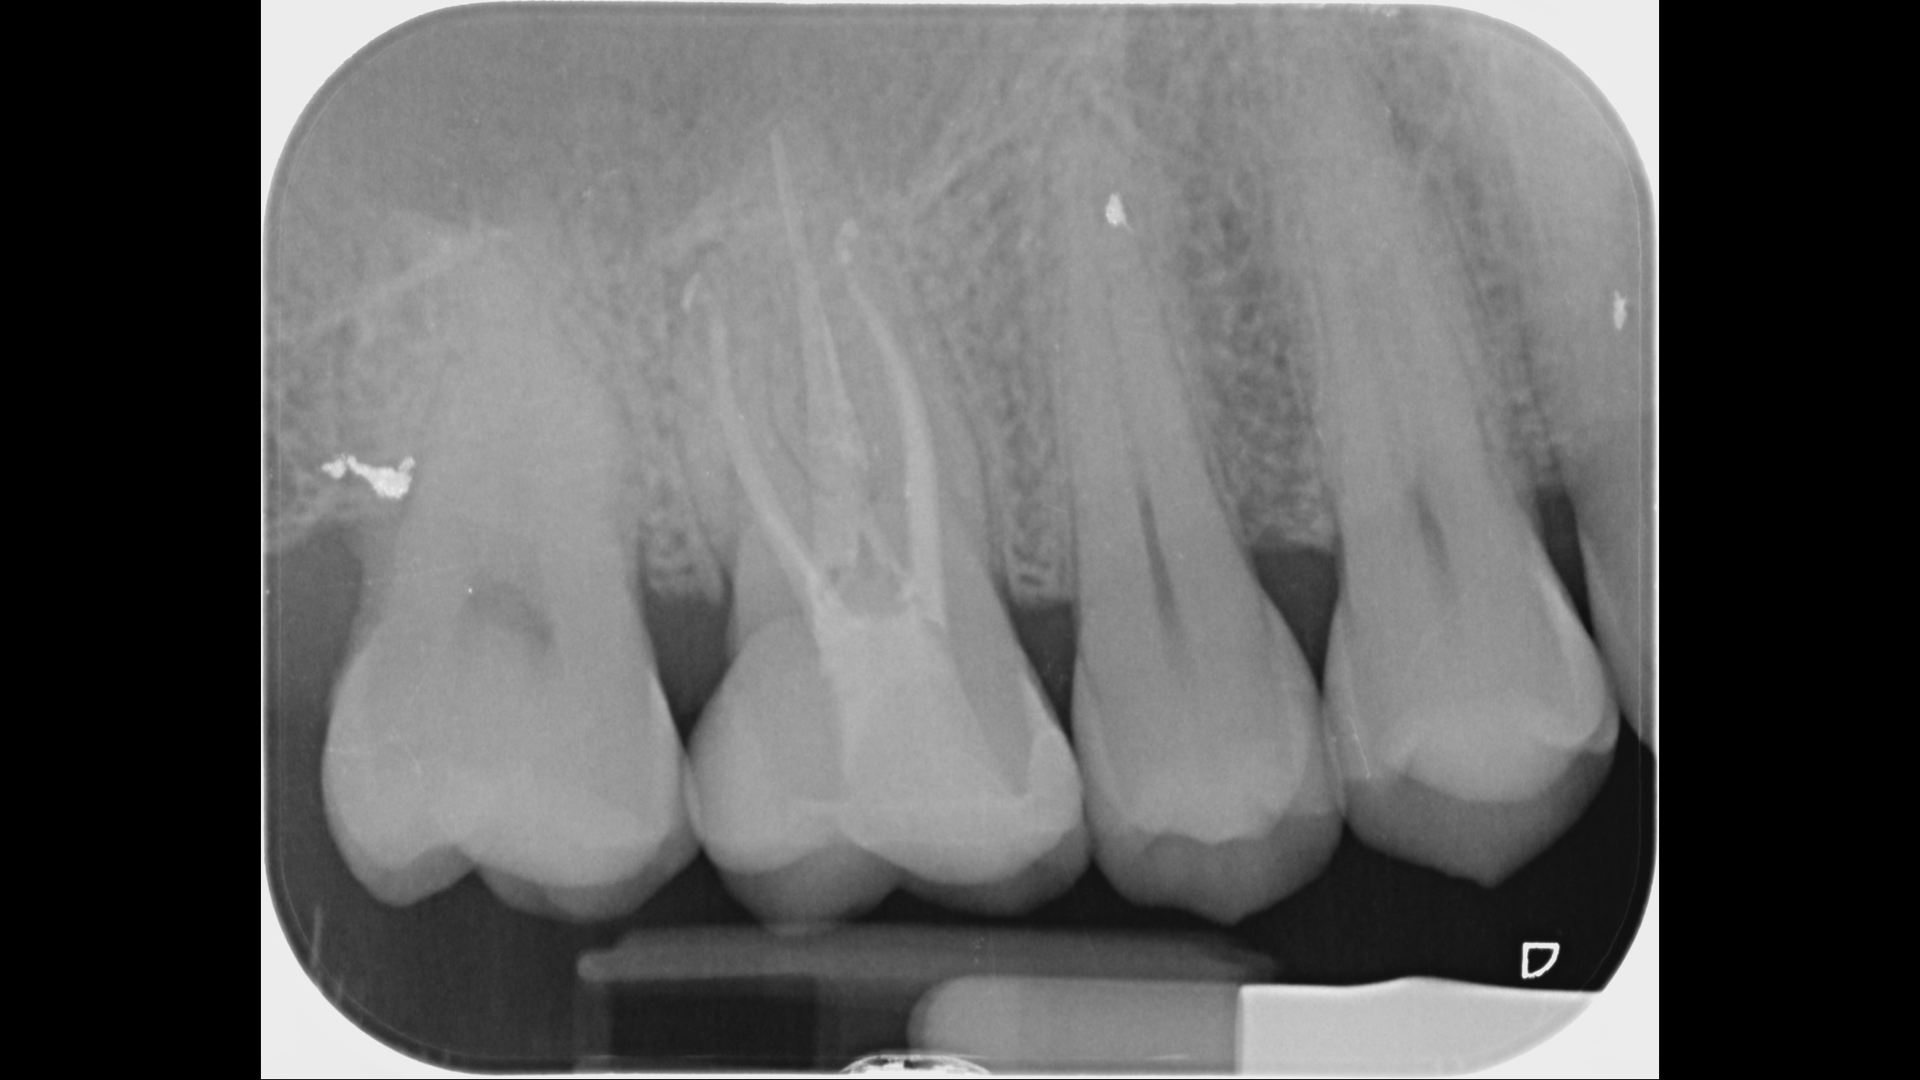

初期X光檢查沒有發現異狀

X光片發現裂痕很靠近牙髓神經